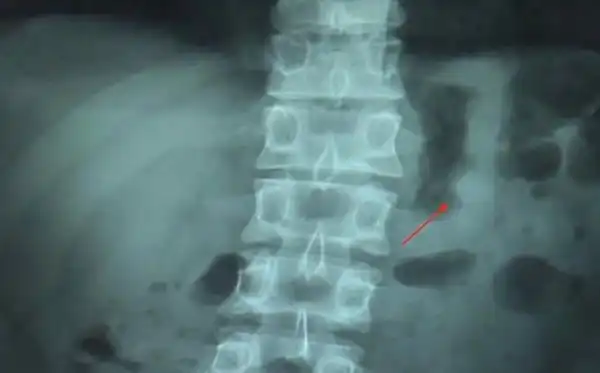

"Daily Mail" пишет, что он обратился к врачам, которые подтвердили, что один из AirPods сейчас как раз находится в его пищеварительной системе. Парню порекомендовали принять слабительное и наушник действительно вышел естественным путем уже к вечеру.